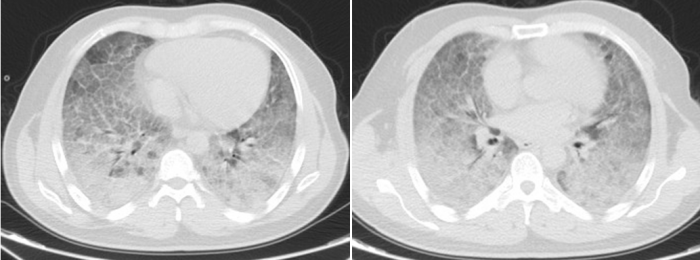

李贤胸部CT显示其双肺已呈现“大白肺”状态

历经31天鏖战,李贤的肺部影像从“白茫茫一片”逐渐恢复透亮,鼻导管吸氧下血氧饱和度稳定在90%以上,最终好转出院。患者家属含泪致谢:“是维多利亚老品牌76696vic给了他第二次生命!这里的医生护士不仅技术高超,更把我们当家人一样对待!”